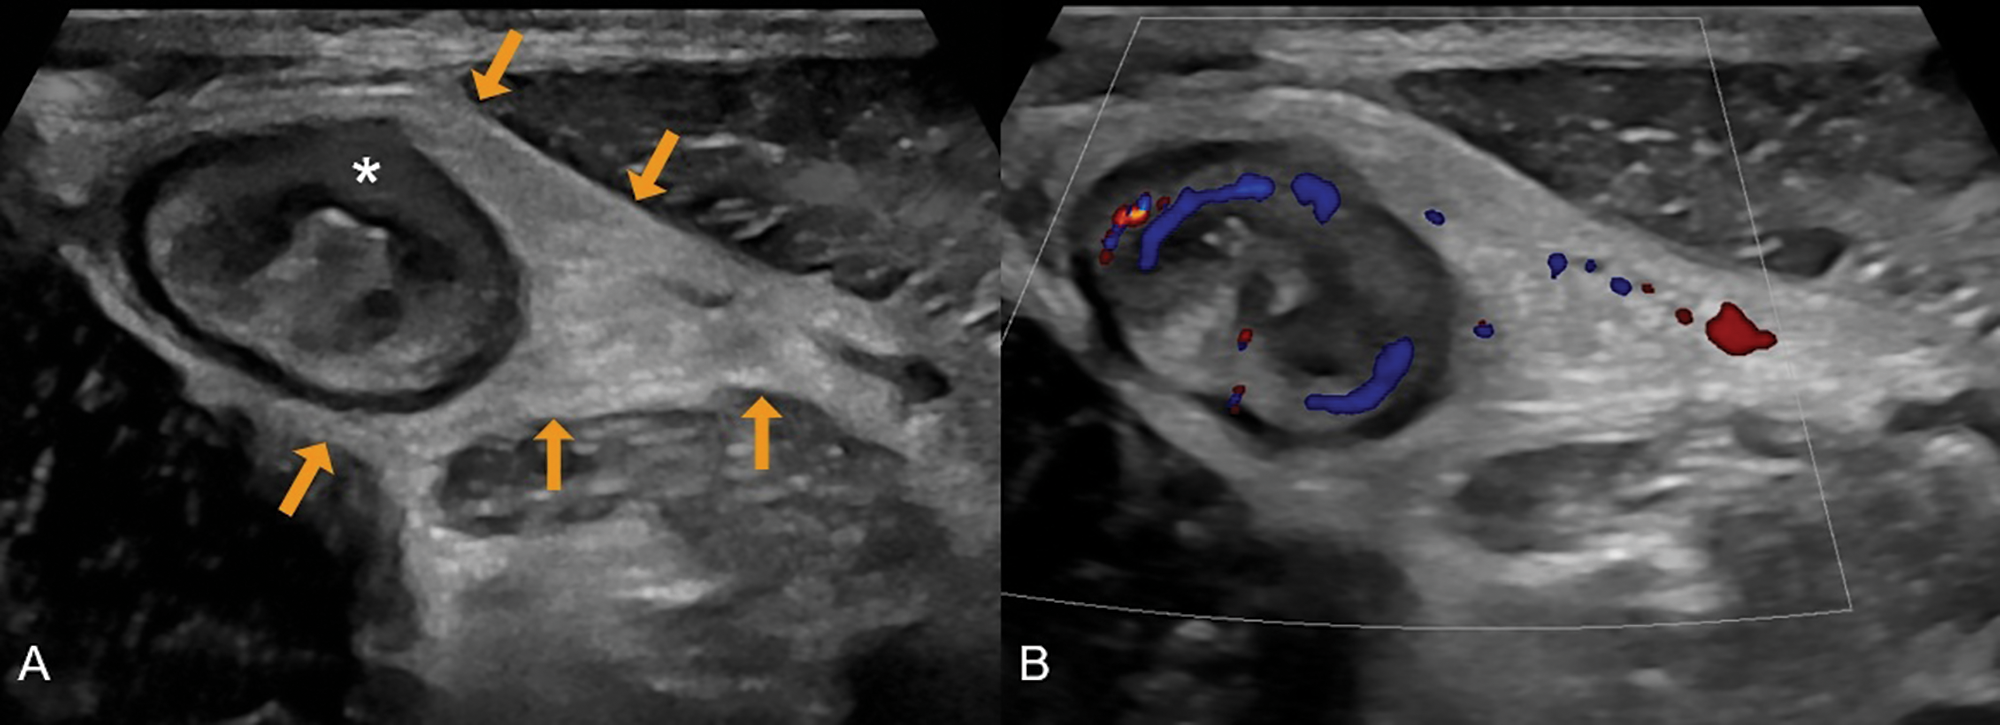

On MRE, active Crohn’s disease is characterized by (1) bowel wall thickening (> 3 mm in distended loops), (2) high mural T2 signal intensity indicating oedema, (3) increased vascularization reflected by mural hyperenhancement and engorged vasa recta (“comb sign”), (4) ulcerations visible as small mural defects, and (5) perimural inflammation seen as high T2 signal intensity in the mesenteric fat (Figure 1). On IUS, the key features include (1) bowel wall thickening (>3 mm), (2) loss of mural stratification due to oedema, (3) increased (extra)mural vascularity on colour Doppler, (4) ulcerations, and (5) hyperechoic mesenteric fat and/or free fluid adjacent to the inflamed bowel segment (Figure 2) [1, 4].

Figure 2

A 31‑year‑old male with newly diagnosed Crohn’s disease. (A) Greyscale ultrasound shows a thickened terminal ileum with extensive loss of mural stratification (asterisk) and hyperechoic fat wrapping (arrows). (B) Colour Doppler demonstrates increased vascularity in the ileal wall and adjacent inflamed fat.